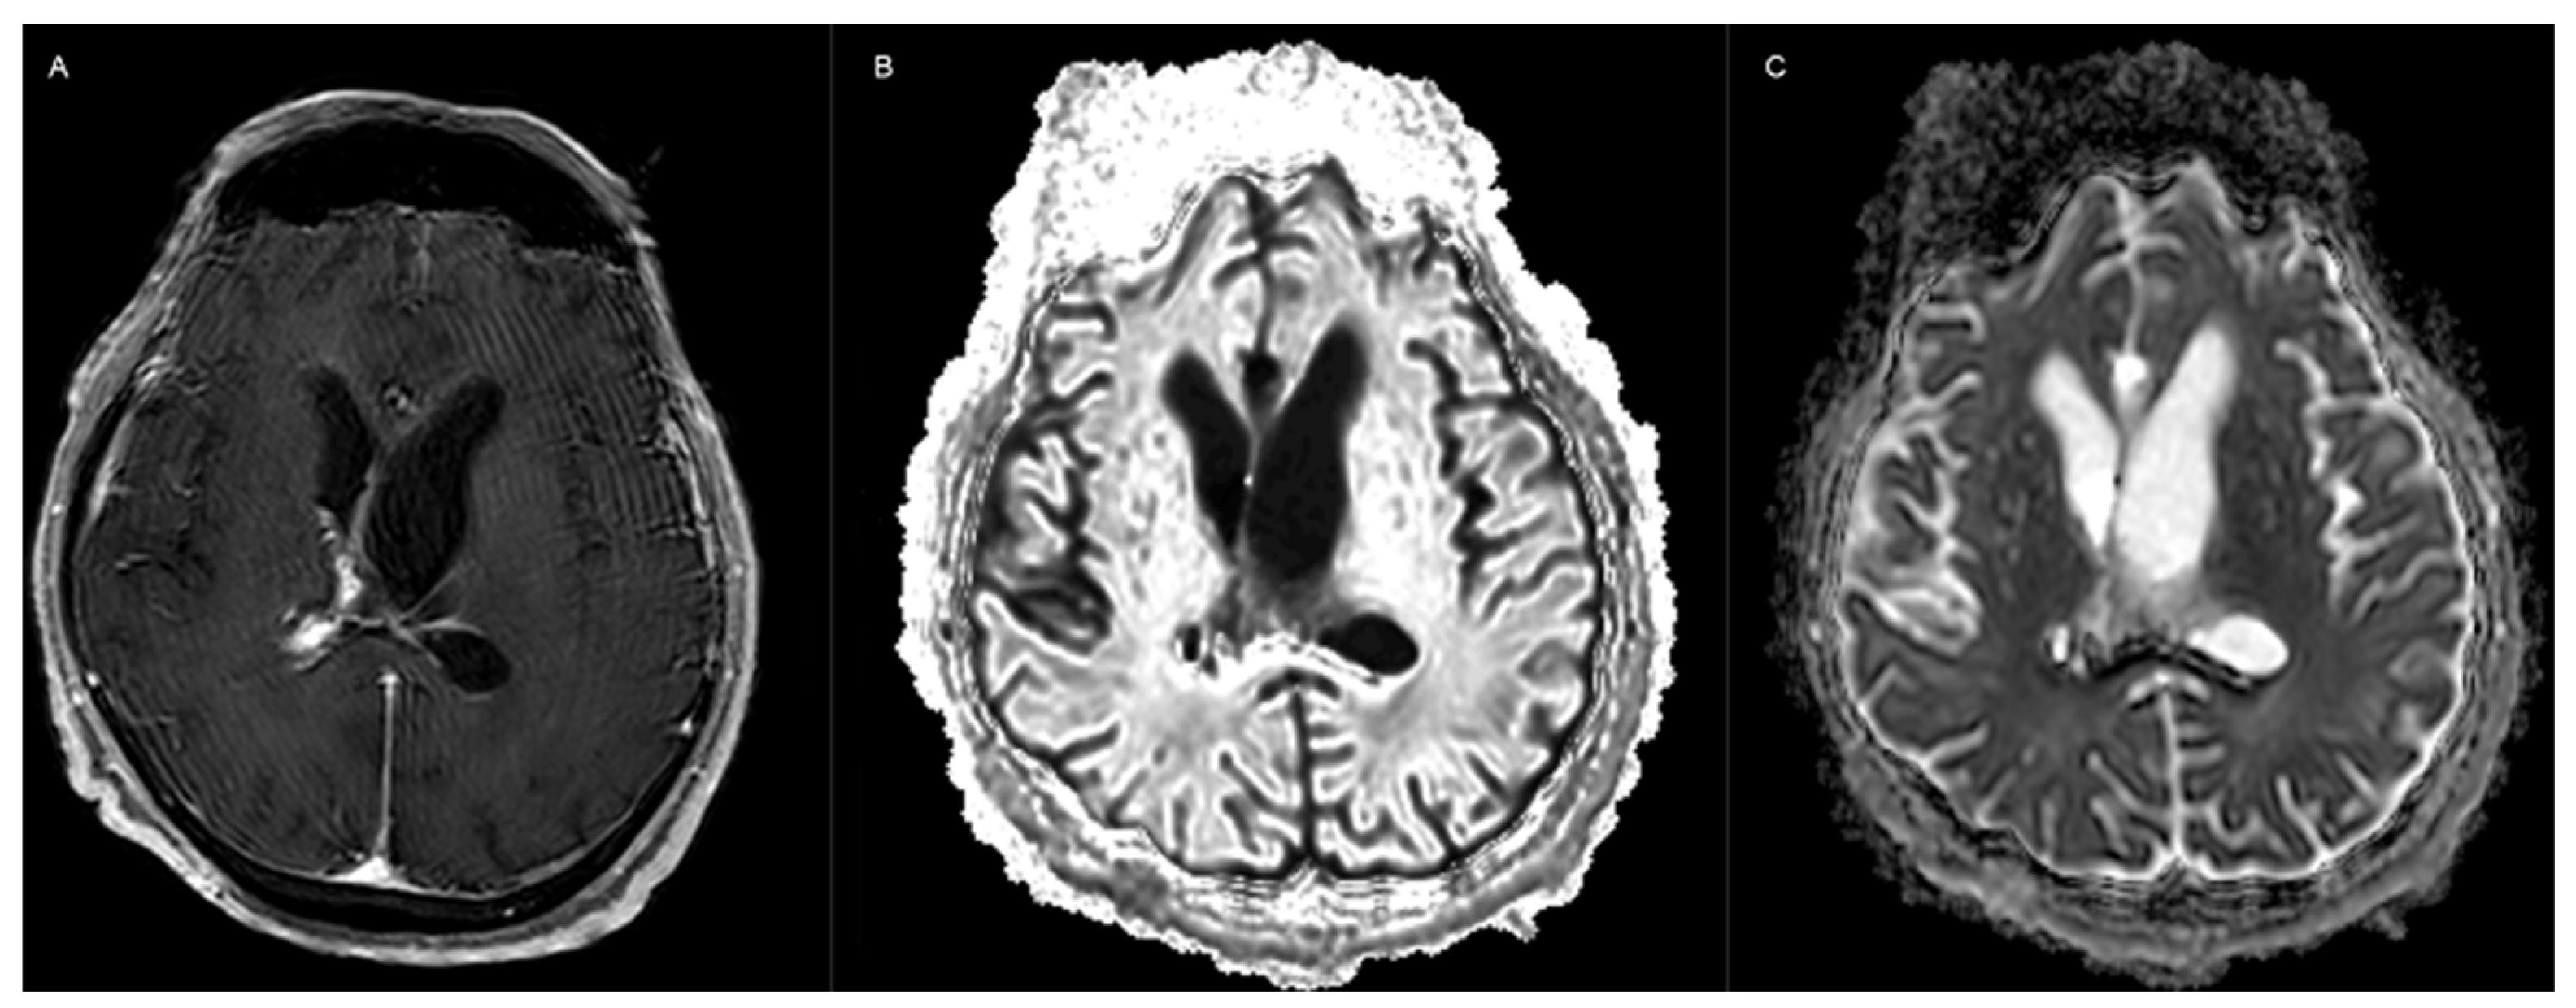

| Sridharan et al., 2024 [31] | Headache and vomiting | Multiple procedures, VP shunt | Turbid csf, no cells | NR | MRI # | S:E, LAmB | LAmB + it LAmB, 28 d | Survival |